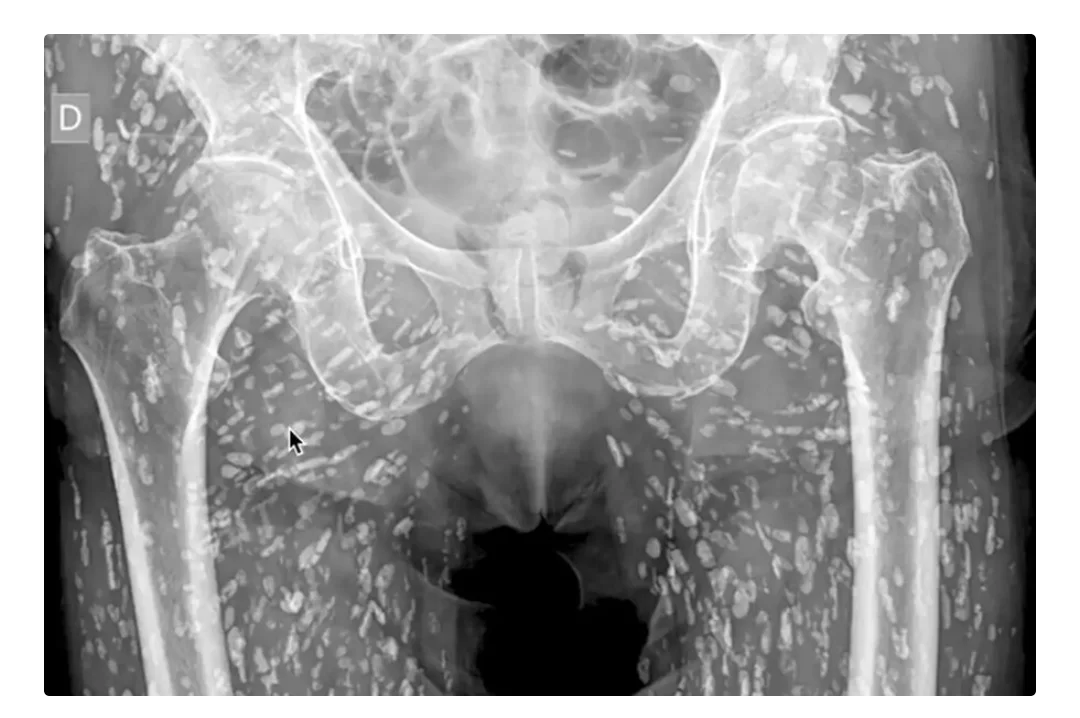

Доктор Сэм Гали, специалист по неотложной помощи, опубликовал этот снимок как напоминание о хрупкости человеческого тела. Белые точки, усеявшие таз и ноги пациента, — это кальцинированные цисты, кладбище погибших паразитов, которых организм навечно замуровал в твердые оболочки.

Диагноз — цистицеркоз. Но как это случилось? Пациент не просто съел плохое мясо. Он проглотил яйца паразита (например, с немытыми овощами, грязной водой или через немытые руки). В желудке из яиц вылупились личинки, которые прогрызли стенки кишечника и с кровотоком разлетелись по всему телу, осев в мышцах. Пациент жил обычной жизнью, не подозревая, что стал живым инкубатором.